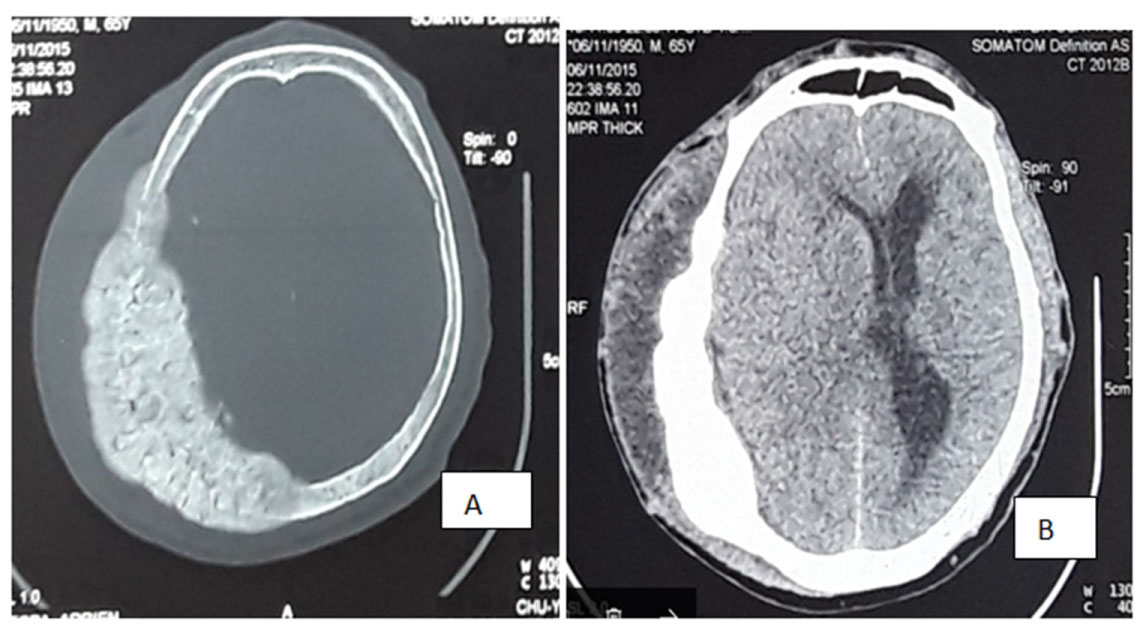

Mr. O.S, is a 55-years-old man who presented with difficulty in passing urine characterized by poor stream, straining on micturition and nocturia of 7 to 10 times per night. There was progressive occipital swelling which was painless with no neurological symptom. No history of prostate cancer in his family. The general condition of the patient was good. There was well-circumscribed, painless occipital mass with normal overlying scalp.

On digital rectal examination, there was enlarged prostate, which was hard and nodular. Total PSA was 715.10 ng/ml and histology of biopsy samples of the prostate revealed adenocarcinoma of the prostate, Gleason score 8 (4 + 4). The kidney function was normal. Brain CT showed a marked occipital osteolytic lesion with significant loss of bone substance (Figure 3).

Figure 3: Brain CT showing occipital osteolytic metastatic lesions A) Bone window depicting discontinuity of the two occipital plates; B) Soft tissue window showing intracranial mass compressing on the brain parenchyma. View Figure 3

Patient had anti-androgen therapy with Cyproterone acetate 300 mg/day as patient cannot afford medical castration and he also refuses surgical castration. The patient was seen after a month with a total PSA of 80 ng/ml. There was also improvement in the urinary symptoms and reduction of the occipital swelling. At 3 months, PSA increased to 128 ng/ml and serum testosterone was 0.2 ng/ml. Check-up CT brain revealed an increase of the initial occipital lesion with appearance of a new osteolytic mass in the left temporal region.